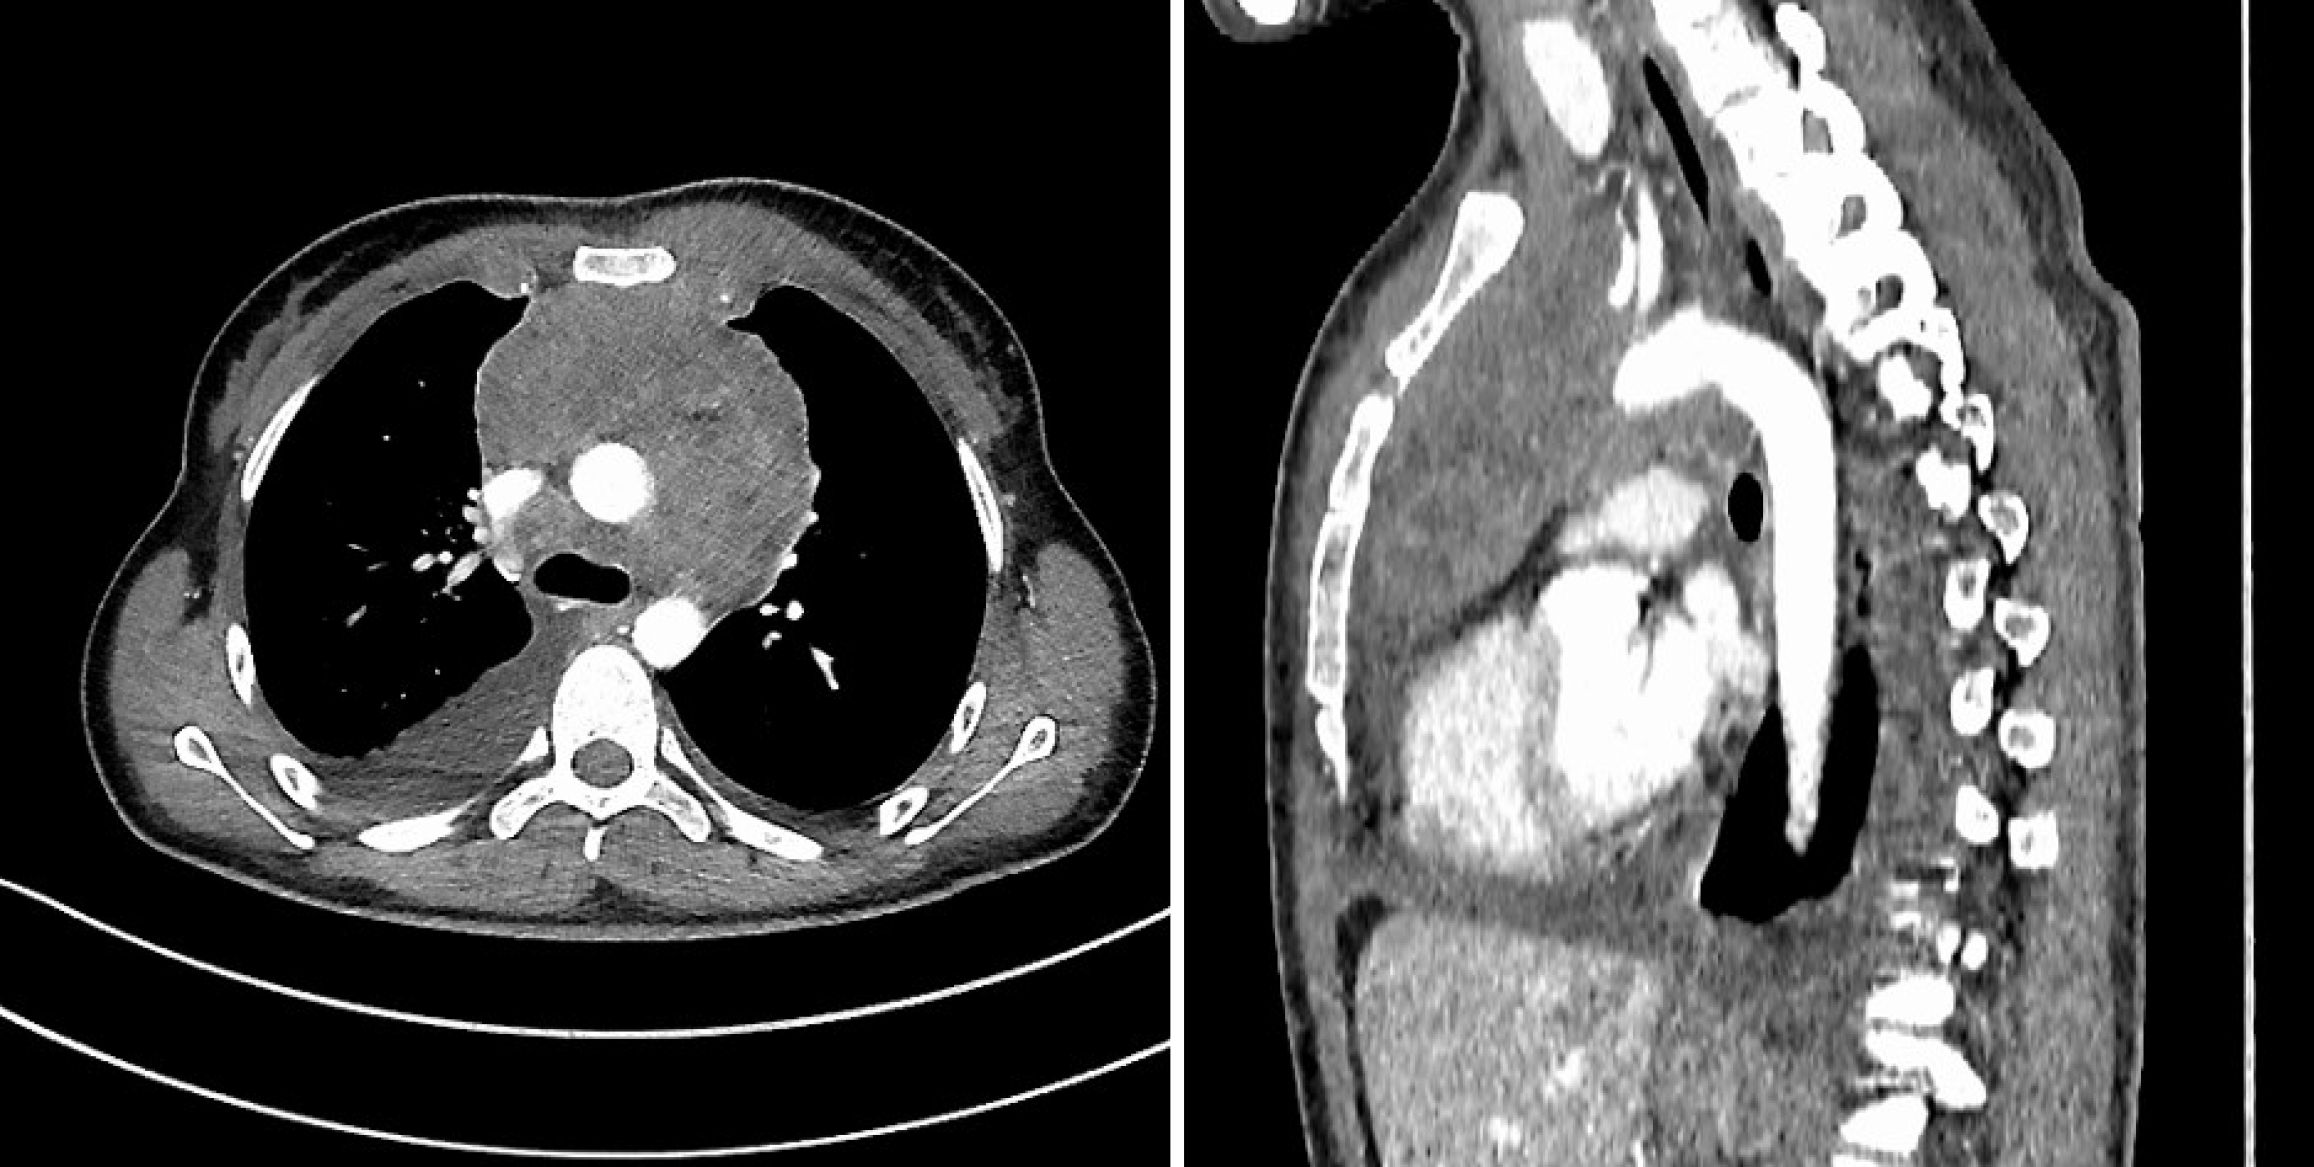

Figure 2 Patient B’s initial chest computed tomography scan demonstrating a bulky mass in the anterior mediastinum.